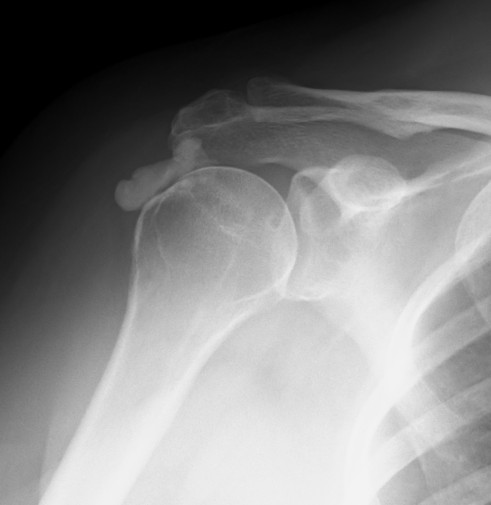

X-ray

Supraspinatous CalciumCalcific Tendonits LateralSupaspinatous Large Deposits

Supraspinatus calcification